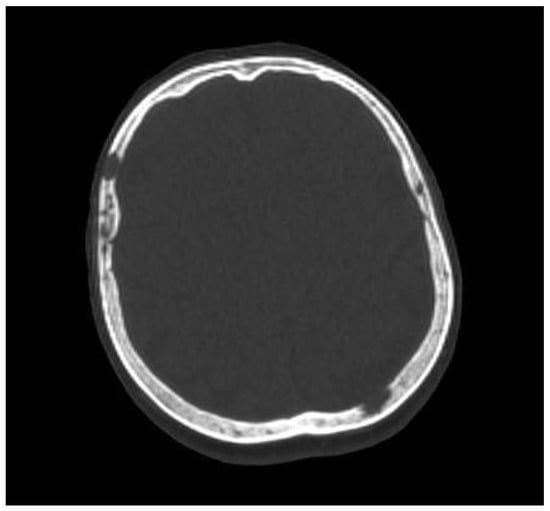

The presence of one or more sites of osteolytic bone destruction, at least 5 mm or greater in size, fulfills the criteria of bone disease in MM (CRAB), and therefore makes it necessary to initiate treatment (Figure 1, Figure 2 and Figure 3). In the case of smaller suspicious lesions seen in WBLDCT, they should be imaged within 3–6 months with CT or MRI to avoid overinterpretation [21,22].

Figure 3. A 65-year old woman with multiple myeloma, presenting some lytic lesions in the bones of the skull on whole-body low-dose computed tomography. Source: Radiological Diagnostics Center, The National Institute of Medicine of the Ministry of Interior and Administration, Warsaw, Poland.